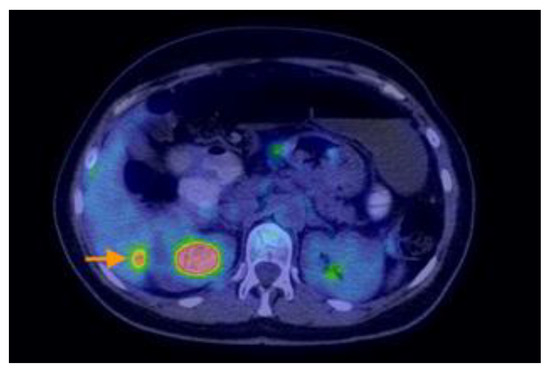

3.2.3. Imaging Findings, Diagnosis, and Differential Diagnosis

3.1.5. Appendiceal Mucocele with Peritoneal Dissemination Mimicking an Ovarian Tumor with Peritoneal Carcinomatosis

- Ayadi, C.; Naggar, A.; Andour, H.; Chraa, F.Z.; Jerguigue, H.; Latib, R.; Omor, Y. Appendiceal mucocele with pseudomyxoma peritonei mimicking ovarian tumor with peritoneal carcinomatosis. Radiol. Case Rep. 2022, 17, 3000. [Google Scholar] [CrossRef] [PubMed]